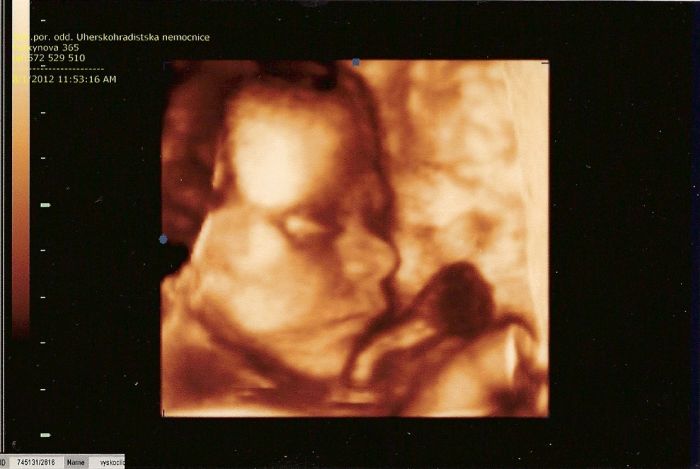

Taky jsem včera zažila jednu důležitou, připadalo mi, že ten UZ včera mohla udělat ona, jak radila doktorce. Doma jsme to shlédli a vyhozené peníze. Doktorovi to řeknu, že to teda neumí, ať je to v té nemocnici někdo naučí, vyhozené peníze!! malá tam má hlavičku jak vetřelec, pořád ji utíkal obraz a neuměla si to včas stopnout!!

Holky, je to samý stín, o moc hezčí to není ani na DVD...